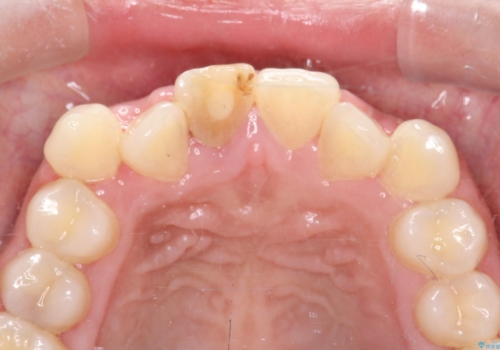

- セラミック矯正希望で来院された患者さんです。

歯周組織の状態が悪く、この状態ではきれいにかぶせものを入れることができないため、仮歯にかえてある程度見た目を改善した上で、歯周基本治療を進めることに。

いざ型どりしていくというタイミングで、前歯の大きさが違いすぎるのが気になるとのことで歯周外科治療(アピカリ)にて歯肉のラインを整えることに。